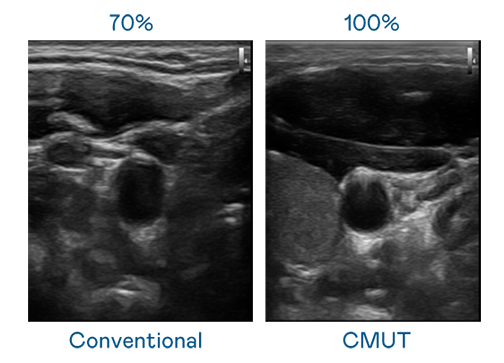

CMUT 技术是一种用电容式微机电元件来产生超音波讯号的技术。与传统 PZT 压电式技术相比,CMUT 频宽增加 30%,更宽频的超音波讯号让影像解析度大幅提升,是实现高影像品质医疗超音波扫描、促进精准医疗发展的关键技术。

超音波影像的解析度高低,首先取决于探头能发出的讯号频宽。mile米乐 CMUT 可提供高清晰的超音波讯号,提供高频宽、高灵敏度、影像纹理细节更高的超音波影像,协助医护人员缩短影像判读时间及利用精准的医疗影像进行诊断。